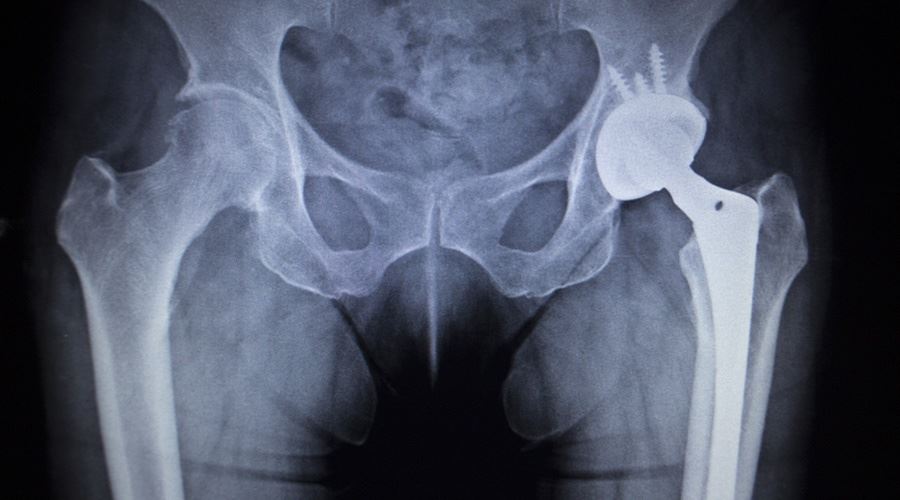

December 4, 2017 Jury Awards Patients Millions in Defective Hip Lawsuit Categories: Product Liability